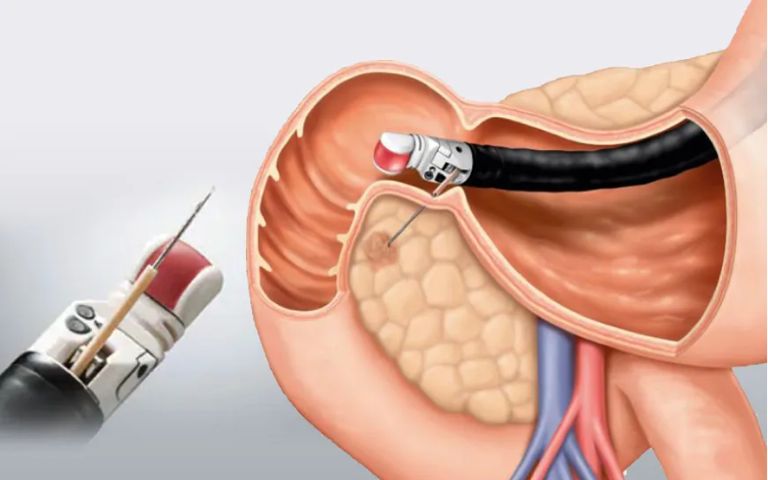

膵臓に腫瘍がある場合には内視鏡の鉗子孔から穿刺針を出して、胃壁や十二指腸壁を貫いて、膵臓の細胞を取ります(図3)。

▲図3:吸引細胞診

最近では穿刺針の改良により、1回の穿刺にて十分量の組織が取れるようになってきました。合併症として出血、穿孔、膵炎等の可能性もありますが、欧米では日帰り手術として行われています。当診療所でも症例によりますが、細胞採取は可能です。